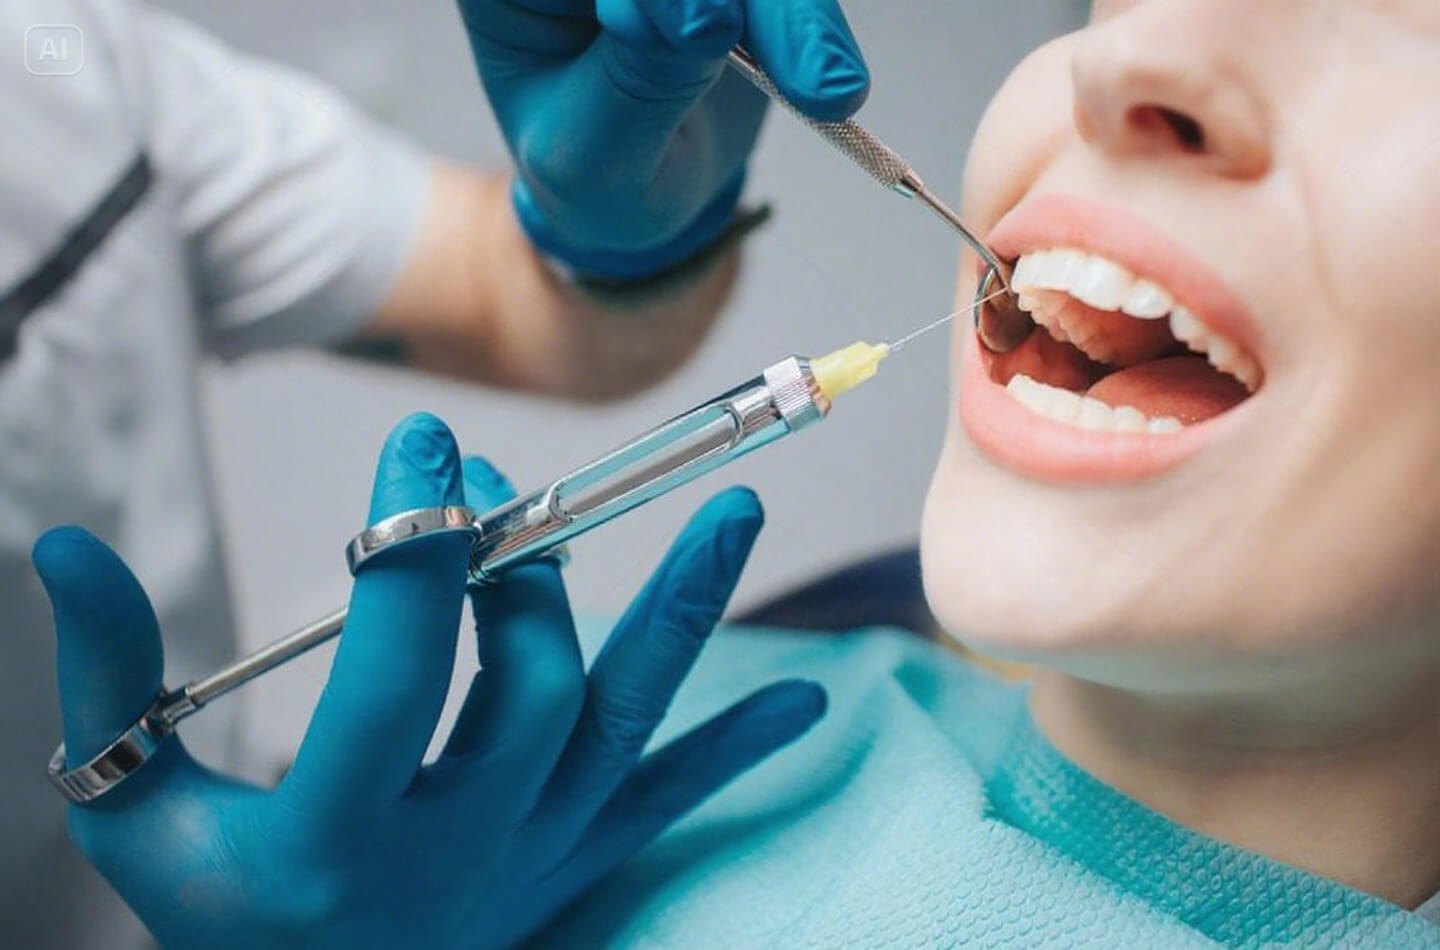

把骨釘打進牙床,光想像就很痛吧!患者們往往只是聽到骨釘就忍不住開始擔憂,但事實上,實際狀況完全沒那麼可怕!「打骨釘」的過程中,牙醫師會先為您上局部麻醉,且並不會有任何敲打動作,而是像鎖螺絲一樣把骨釘鎖到定位。在麻醉的作用下,理論上患者並不會有什麼感覺,甚至可說是比拔牙還輕鬆的小手術呢!

只是,麻醉消退後,少數患者仍可能會感到疼痛,這時請遵照醫囑適當服用止痛藥,通常約 3 天以內疼痛即可消退。